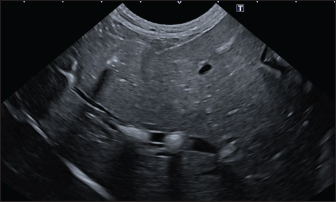

In the branched pattern, mineralizations were usually sub-centimetric or centimetric and they replicated the shape of the intrahepatic biliary tree (Fig. 3). Also in this case, sub-centimetric and centimetric IBTM determined a focal dilatation of the biliary ducts observed in 65.6% of dogs (21/32) (Fig. 4). In six of them (18.7%), we found millimetric IBTM randomly distributed in the liver.

Fig. 4. Ultrasound image of the liver showing centimetric IBTM, generating acoustic shadow, with an aligned pattern. In the image, we can observe a focal dilation of the larger biliary duct, upstream and downstream to the calculi, because of the presence of the choleliths themselves.